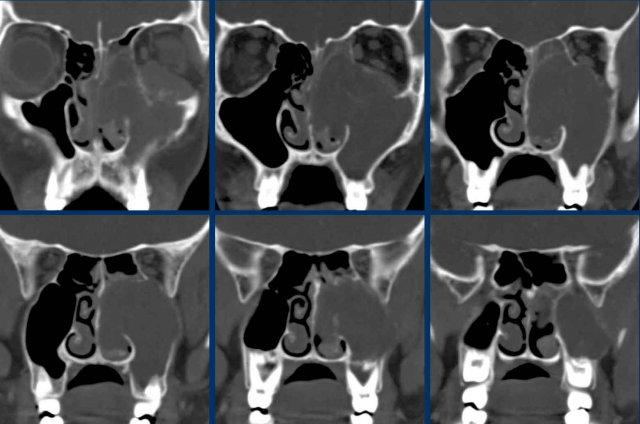

Ung thư biểu mô tuyến

Đây là bệnh nhân có triệu chứng nghẹt mũi tắc nghẽn.

Nếu chỉ mô tả ca này đơn thuần là hình ảnh mờ gần hoàn toàn các xoang cạnh mũi bên phải, bác sĩ lâm sàng có thể dễ dàng nghĩ đây chỉ là một trường hợp viêm xoang thông thường.

Như đã đề cập, dấu hiệu cảnh báo ở đây chính là vị trí định khu bất thường một bên.

Viêm xoang một bên là cực kỳ hiếm gặp.

Hơn nữa, nếu quan sát kỹ, có thể thấy hình ảnh phá hủy vách ngăn mũi — đây là dấu hiệu cảnh báo thứ hai.

U nhú đảo ngược

Đây là một trường hợp khối u một bên khác.

Khối u ngấm thuốc có cường độ tín hiệu cao hơn so với xoang hàm bị tắc nghẽn.

Lưu ý rằng khối u có bờ thùy múi.

Đặc điểm này thường gặp trong u nhú đảo ngược, tuy nhiên không có tính đặc hiệu cao và trong mọi trường hợp đều cần thực hiện sinh thiết.

Chẩn đoán cuối cùng: u nhú đảo ngược.

Đây là một trường hợp u nhú đảo ngược khác.

Tổn thương biểu hiện là một khối niêm mạc có bờ thùy múi với hình ảnh ‘cuộn não’.

Trông như hình ảnh các hồi não (đầu mũi tên).

Đặc điểm này có tính đặc hiệu nhất định đối với u nhú đảo ngược.